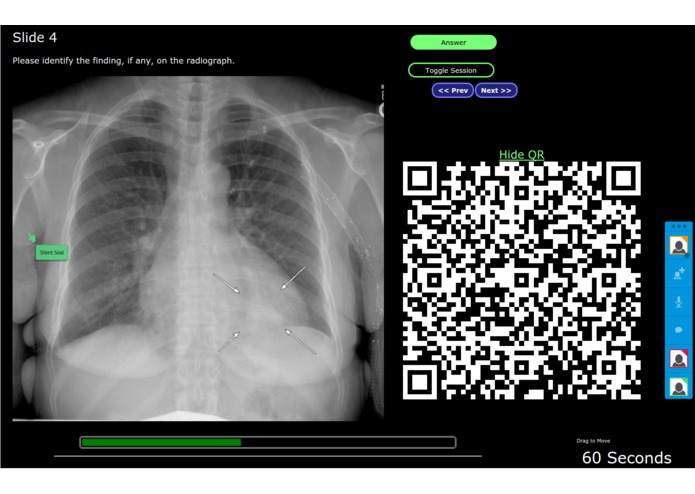

3. A QR code is made available so the audience can use QR scanner on their phone or tablet device to join the discussion. The QR code can be dragged out of the way or hidden.

4. A timer is available so the presenter can "quiz" the audience to log in and point at where the disease is before time runs out.